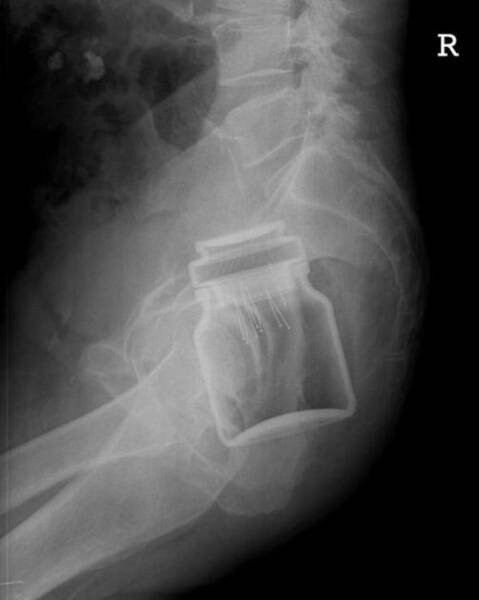

8. Банка из-под растворимого кофе